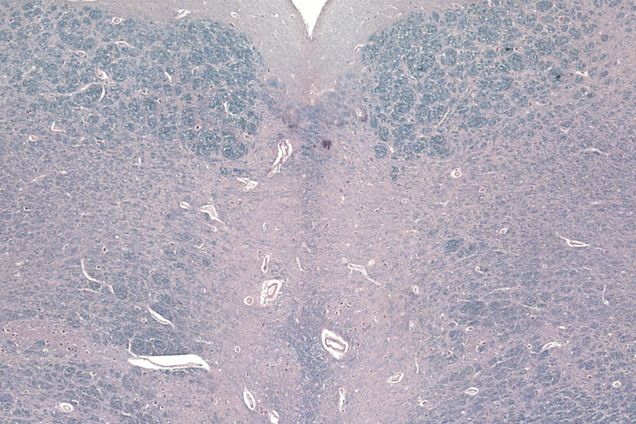

CTE and Alzheimer's Disease

We Know Repeated Head Hits Contribute to CTE—but What about Alzheimer’s Disease?